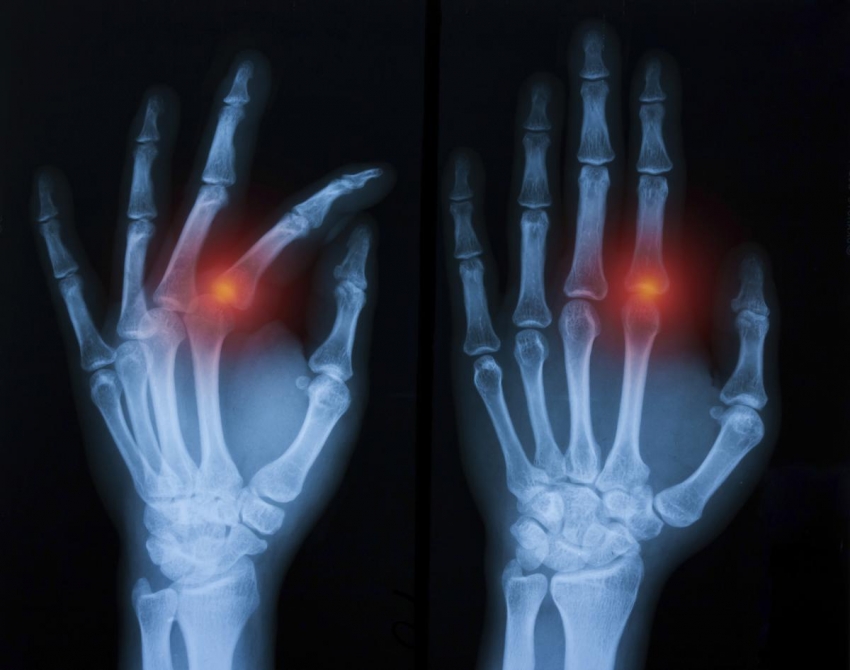

Avulsion Fracture - स्नायू किंवा अस्थिबंध (दोन हाडांना जोडणारी जागा) यामुळे झालेले फ्रॅक्चर.

Fracture Dislocation - सांध्यातील एका हाडाला फ्रॅक्चर असल्याने सांधा निखळणे.

IntraArticular Fracture - हाडासोबतच सांध्याचा पृष्ठभाग सुद्धा फ्रॅक्चर होणे.